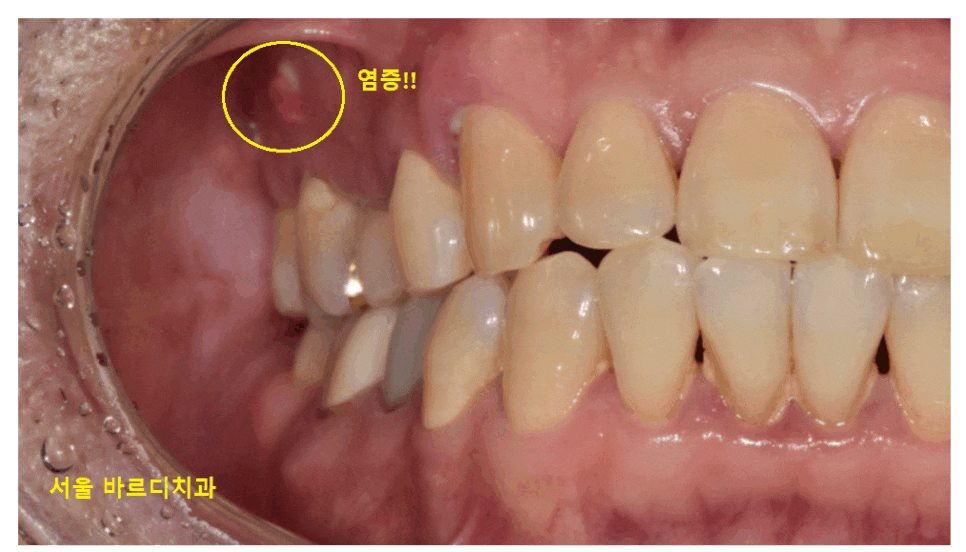

맨 처음 방문하셨을 때 사진입니다.

해당 환자분은 치아가 안좋은걸 느끼셨지만

꾹 참았다 하셨는데요.

23.03.20

잇몸 뾰루지 몇번씩 올라오면 제거하고

약먹고 치료받고

더 쓰고 싶어서 계속 버텼다고 하셨어요.

많이 흔들리고

입에서 염증 맛도 느껴지고 해서

뽑아야할꺼같다 하셨는데요.